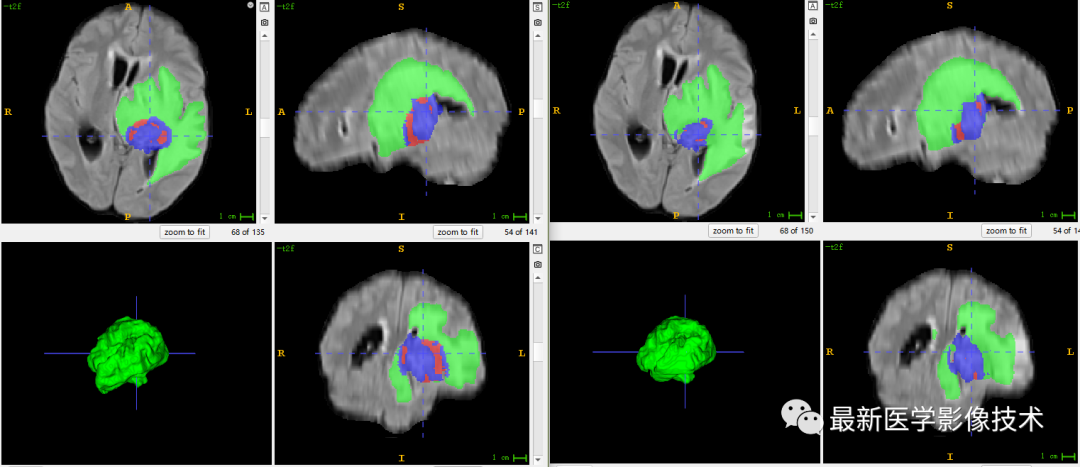

6、验证集分割结果

左图是金标准结果,右图是网络预测结果。